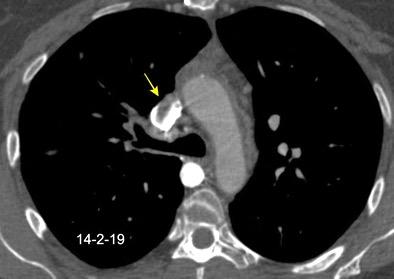

1. Obstrucción por encima de la V Ácigos. (La sangre llega al corazón a través de ella)

2. Obstrucción con participación de la V. Ácigos. (La sangre utiliza otras alternativas para llegar al corazón vía VCI).

Participación de la V. Ácigos como vía principal para llegar a la VCI.

Visible: 88%